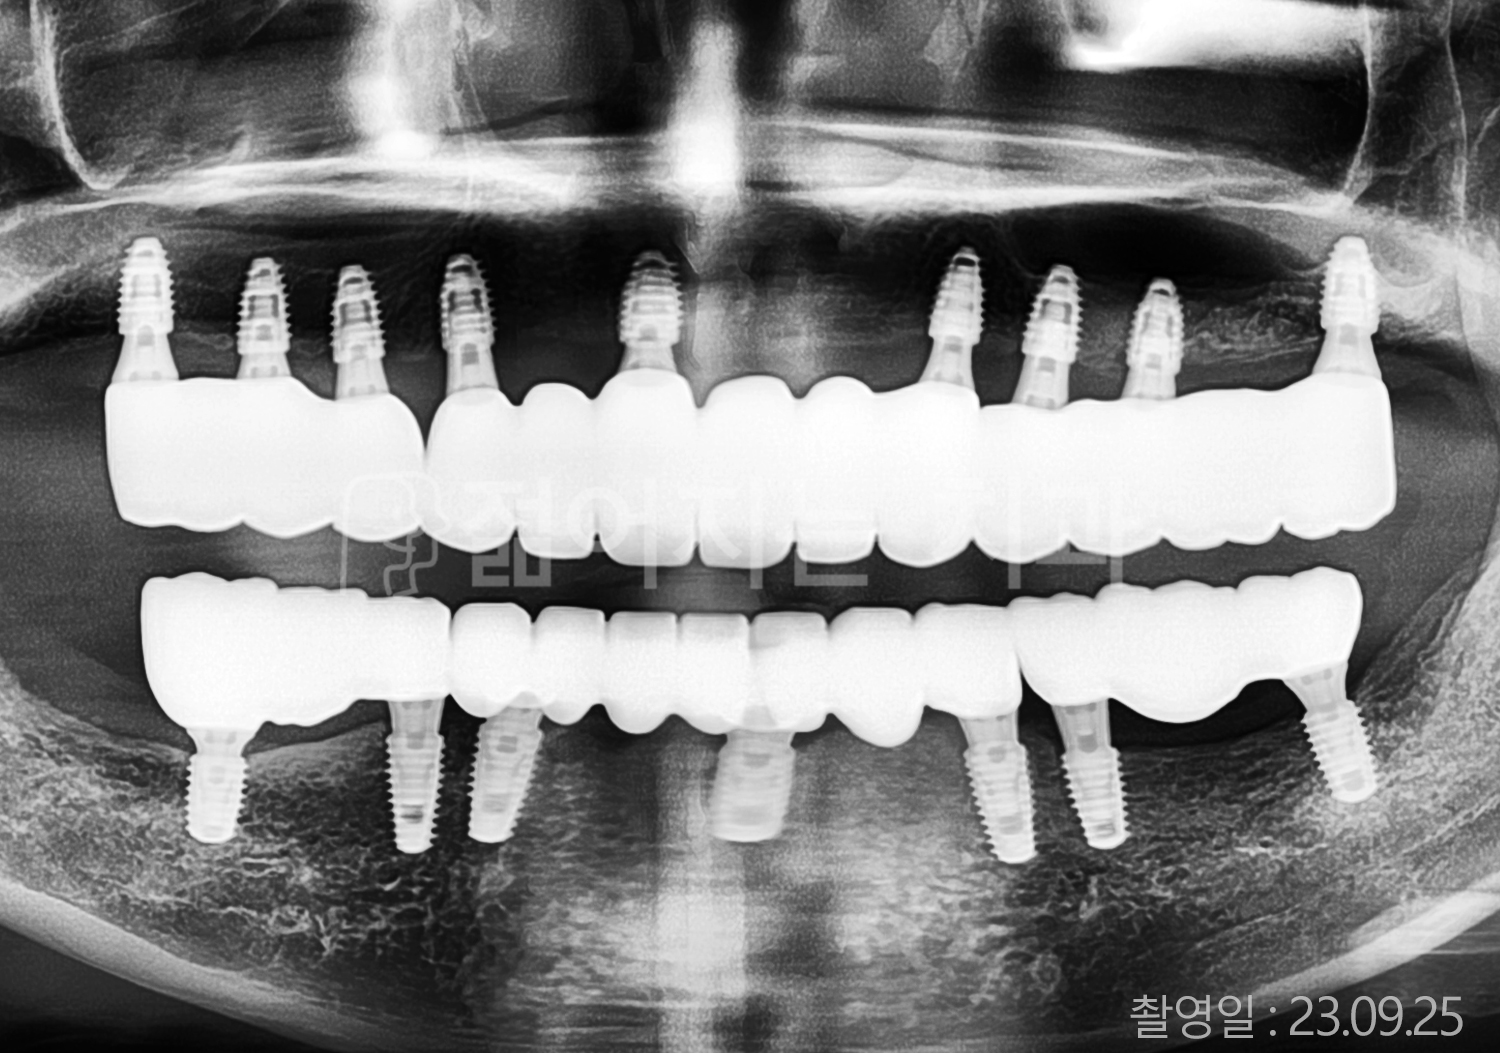

• 50대 고혈압, 당뇨, 고지혈증 전체치아 10개 이상 임플란트

• 60대 골다골증, 간경화 전체치아 10개 이상 임플란트

• 60대 고혈압, 고지혈증 전체치아 10개 이상 임플란트

• 50대 고혈압, 당뇨 전체치아 10개 이상 임플란트

• 60대 고혈압 전체치아 10개 이상 임플란트